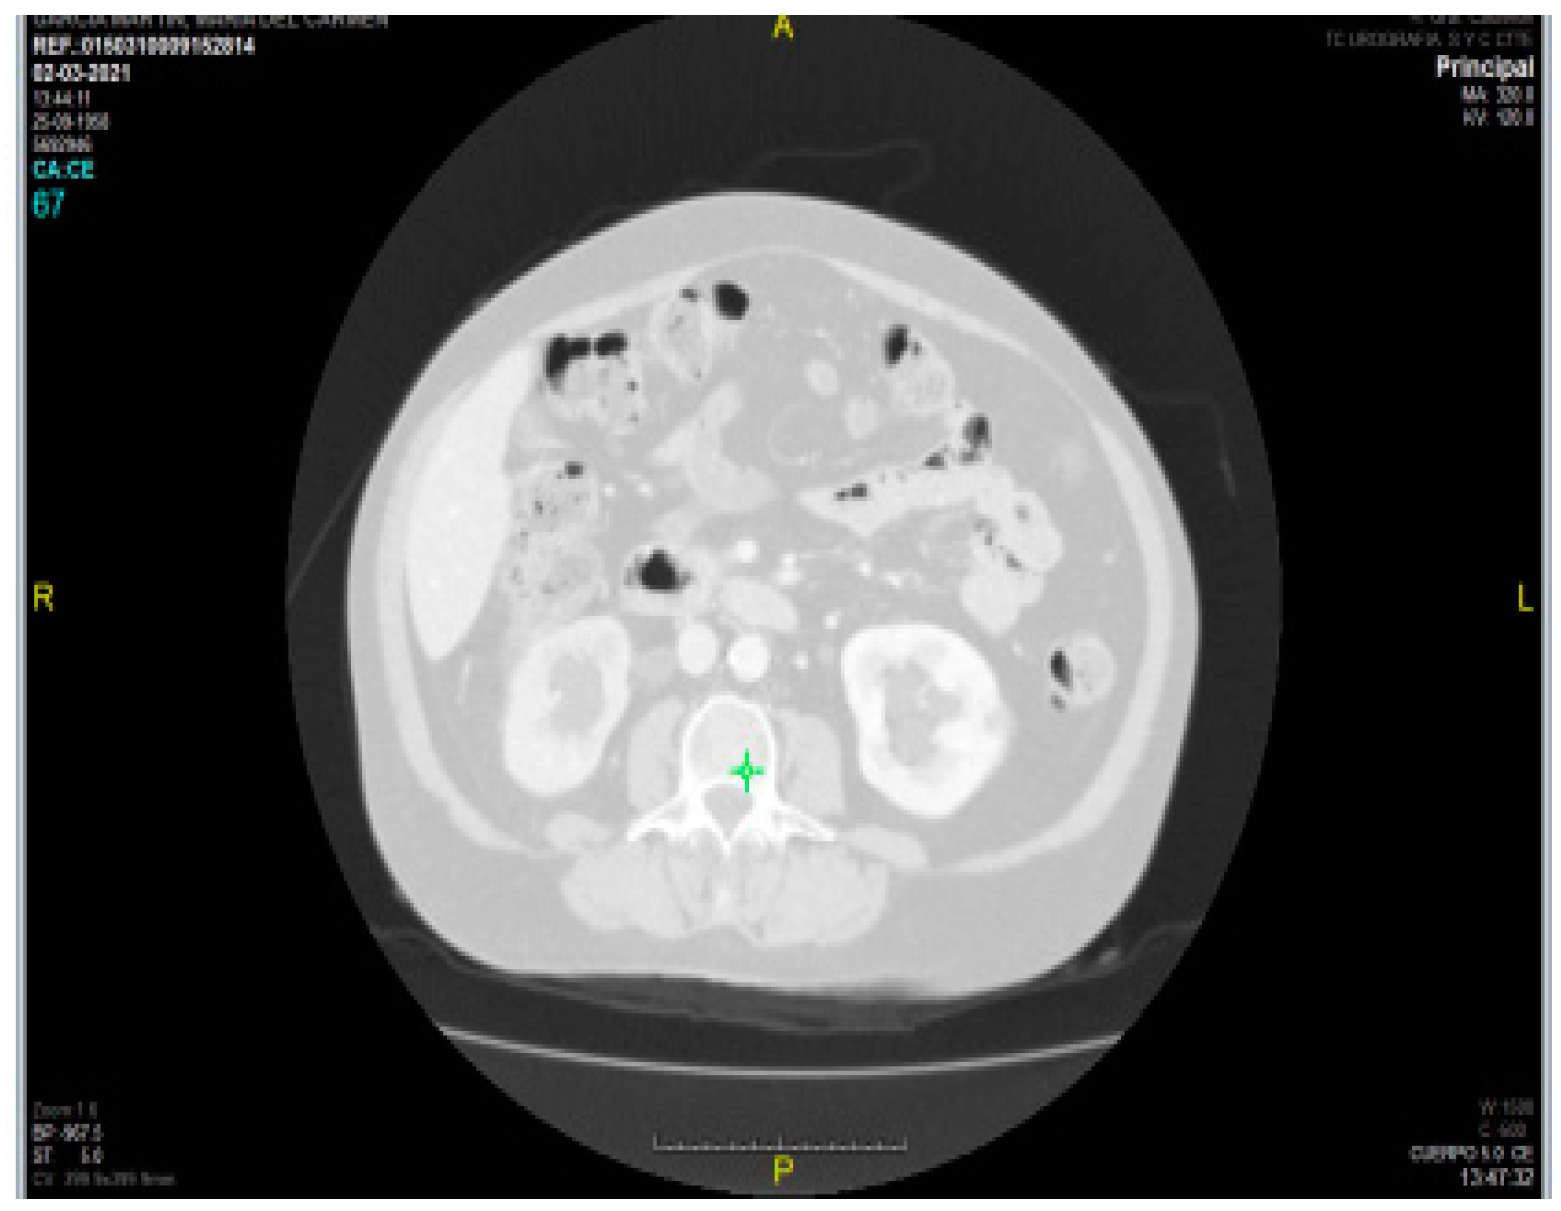

Regarding intramuscular fat mass, in the present study there is a lack of correlation between myosteatosis measured in HU density on CT compared to adipose tissue depth measured by rectus femoris ultrasonography (PMI r -0.040 and SMI r -0.133) and rectus femoris muscle echogenicity (r -0.075 and r 0.118 for SMI and PMI, respectively). This may be due to the method used (with Centricity Universal Viewer v7.0 SP1 0.3), which is a manual method and therefore the HU density varies depending on the amount of contrast used, as can be seen in the two figures (

Figure 7. HU density PMI 70 /

Figure 8. HU density -52).

This is in contrast to semi-automated methods (4) where the use or non-use of contrast does not affect the results.